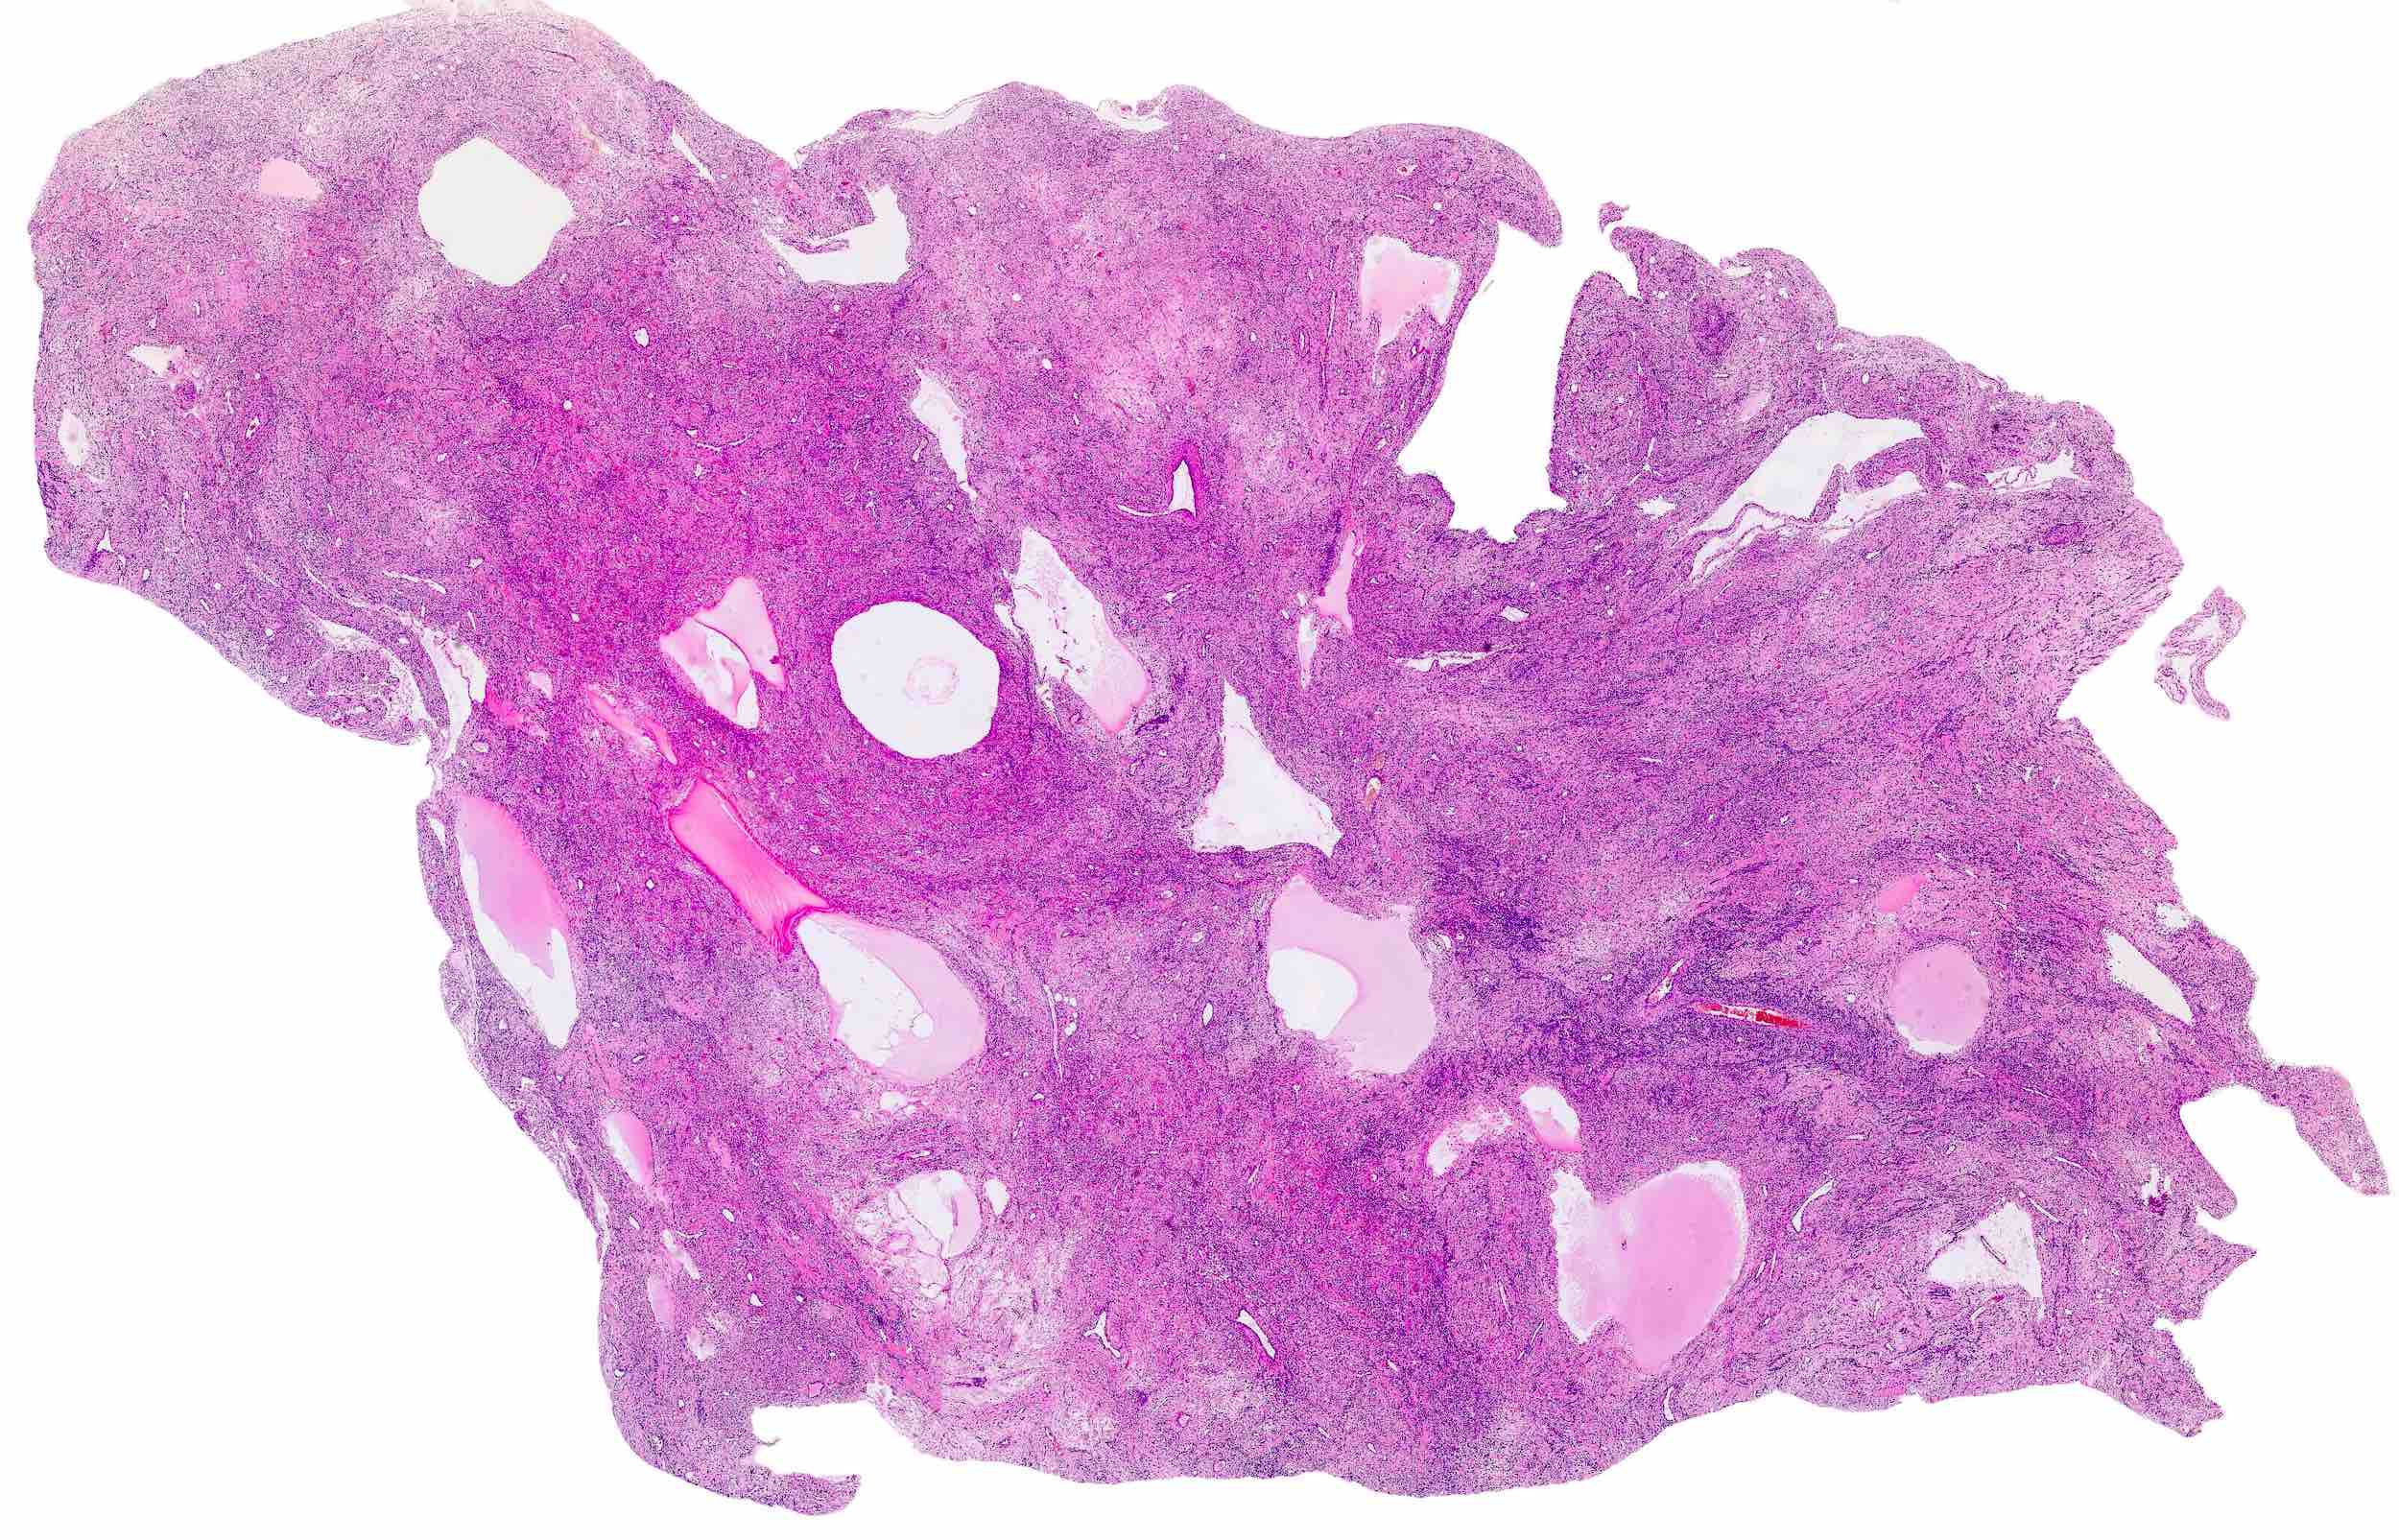

- Rare, benign appearing smooth muscle tumor in lung; may represent hematogenous spread of a uterine leiomyoma or a metastasis of a well differentiated leiomyosarcoma of low malignant potential (Mod Pathol 2006;19:130)

- Usually women 36 - 64 years, mean 44 years, with history of uterine leiomyoma

- Lung is most common site, sparing bronchus and pleura; also reported in lymph nodes, retroperitoneum, skin, bone, spine, skull base, heart

- Usually multiple nodules, up to a few centimeters in size

Microscopic (histologic) description

- Conventional / usual leiomyoma (spindle):

- Well defined borders

- Normocellular

- Intersecting fascicles of monotonous spindle cells with indistinct borders, eosinophilic cytoplasm, cigar shaped nuclei (with tapered ends) and small nucleoli

- Atypia: absent or mild

- Mitoses: rare (in general < 5/10 high power fields)

- Blood vessels with thick walls

- With or without infarct type necrosis, hyalinization, calcification, cystic change

Microscopic (histologic) images

Contributed by Sabrina Croce, M.D., Ph.D., Kristina Doytcheva, M.D., Jennifer A. Bennett, M.D. (Case #508) and @Andrew_Fltv on Twitter